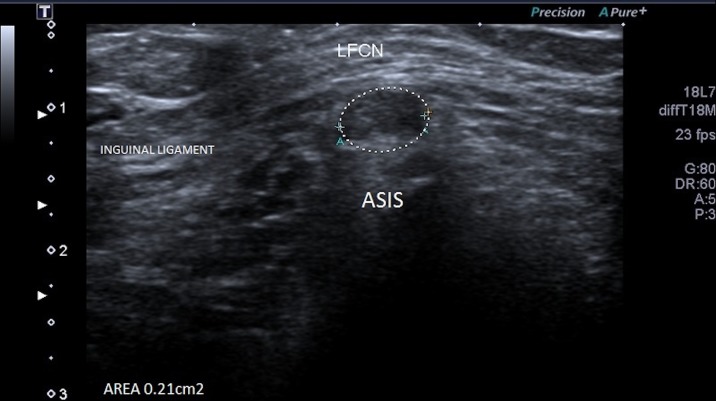

Eight weeks following initial presentation, a focal ultrasound of the groin and left thigh was performed which revealed a thickened and abnormally hypoechoic left lateral femoral cutaneous nerve, measuring 3.4 mm in diameter (figures 1 and 2) compared with 2.2 mm on the right side (figure 3). There was loss of the normal fascicular pattern between the anterior superior iliac spine and the inguinal ligament, consistent with nerve entrapment. At this point, the diagnosis of left meralgia paraesthetica was made.

Figure 2.

Axial view of the left lateral femoral cutaneous nerve (LFCN).